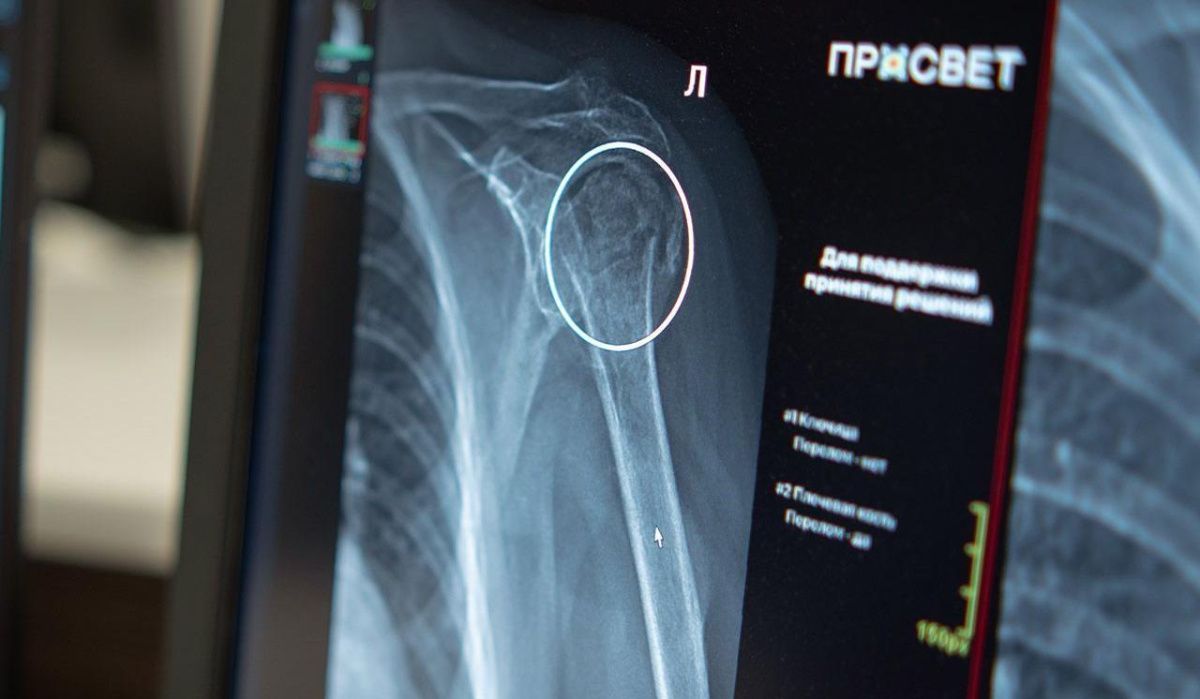

В Москве начал функционировать инновационный сервис, разработанный на основе искусственного интеллекта, для диагностики переломов костей плечевого сустава.

«Алгоритм автоматически выявляет подозрительные зоны и необходимые параметры, ускоряя обработку исследований и повышая точность диагностики травм. Этот сервис на основе ИИ особенно важен в травматологии, где важны оперативность и точность для своевременного назначения лечения и уменьшения риска осложнений. Внедрение искусственного интеллекта в травматологию является очередным этапом в развитии цифровой медицины города. Сервис интегрирован в масштабную систему, где нейросети функционируют по 41 клиническому направлению», — рассказал Юрий Васильев.

В городских больницах, поликлиниках и травмпунктах начнут использовать новый ИИ-сервис для диагностики переломов плечевого сустава. Особая тщательность врача необходима для точного анализа рентгеновских снимков таких травм. Алгоритм содействует быстроте расшифровки изображения, чтобы медики могли сосредоточиться на важных клинических изменениях.

Как отметил главный рентгенолог Москвы, плечевой сустав — одна из наиболее сложных анатомических областей для интерпретации рентгеновских снимков. На точность визуализации влияют даже незначительные позиции пациента при исследовании. В этих условиях необходима внимательность со стороны врача. Алгоритм, который выполняет роль дополнительного фильтра, станет надежным помощником, повышающим точность анализа.